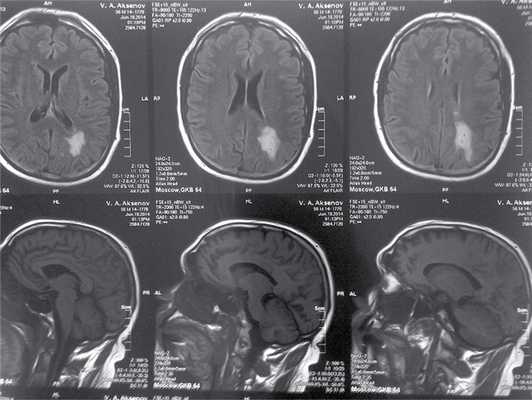

При ультразвуковом дуплексном сканировании брахиоцефальных артерий был выявлен нестенозирующий атеросклероз. Результаты тональной пороговой аудиометрии соответствовали физиологической норме. При магнитно-резонансной томографии (МРТ), выполненной в том числе в режиме DWI и проведенной спустя 10 дней после третьего приступа головокружения, были выявлены изменения, соответствующие недавно перенесенному ишемическому инсульту в области теменно-затылочных отделов левого полушария мозга (см. рисунок).

Магнитно-резонансная томограмма пациента А. Ишемический инфаркт в теменно-затылочной области левого полушария головного мозга.

Принимая во внимание анамнестические данные и результаты МРТ головного мозга, можно предположить связь между выявленными при МРТ изменениями и приступами головокружений. Таким образом, причиной инсульта может быть атеротромбоз задней ветви левой средней мозговой артерии, первоначально проявлявшийся двумя однотипными эпизодами транзиторных ишемических атак, а впоследствии, по мере прогрессирования, приведший к формированию инфаркта головного мозга.

В приведенном выше клиническом наблюдении обращало на себя внимание отсутствие при нейровестибулярном исследовании признаков периферической вестибулярной дисфункции (отрицательная проба Хальмаги), несмотря на ощущаемую пациентом небольшую неустойчивость. Кроме того, не было выявлено слуховых нарушений, что делало маловероятным дебют синдрома Меньера. Отсутствие анамнестических указаний на рецидивирующие приступообразные головные боли исключало мигрень-ассоциированный характер головокружения. Эти обстоятельства, а также наличие факторов риска цереброваскулярных заболеваний (артериальная гипертония, мужской пол, возраст) делают необходимым проведение нейровизуализации. Выявленные при МРТ изменения свидетельствуют об ишемическом инсульте, механизм которого остается не до конца ясным, несмотря на проведенные впоследствии исследования.

Основываясь на имеющихся на сегодняшний день данных о вестибулокортикальных связях, в качестве причины развития вестибулярных симптомов у вышеописанного пациента можно предположить повреждение пути, связывающего вестибулярные ядра через мозжечок, вентролатеральные ядра таламуса с корой теменной области.